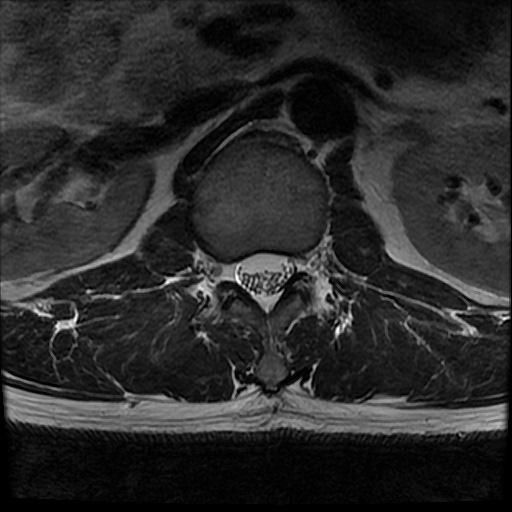

허리 MRI 전문가분들 의견부탁드립니다.

이번에 허리 MRI찍었는데

상태 어떤지 고견 여쭙습니다.

• 4번 째 사진

큰 이상이나 문제점은 없어 보이는 것으로 생각되는데요, 허리통증이 지속되는 경우에는 반드시 디스크 질환에 의한것은 아닐 수 있습니다.

현재로썬 디스크 상태는 심하지않는것으로 확인이 됩니다.